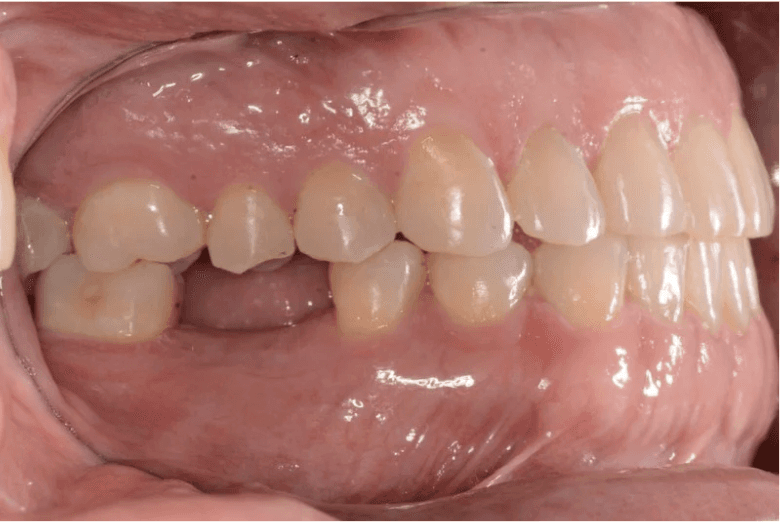

Final results

INTRAORAL